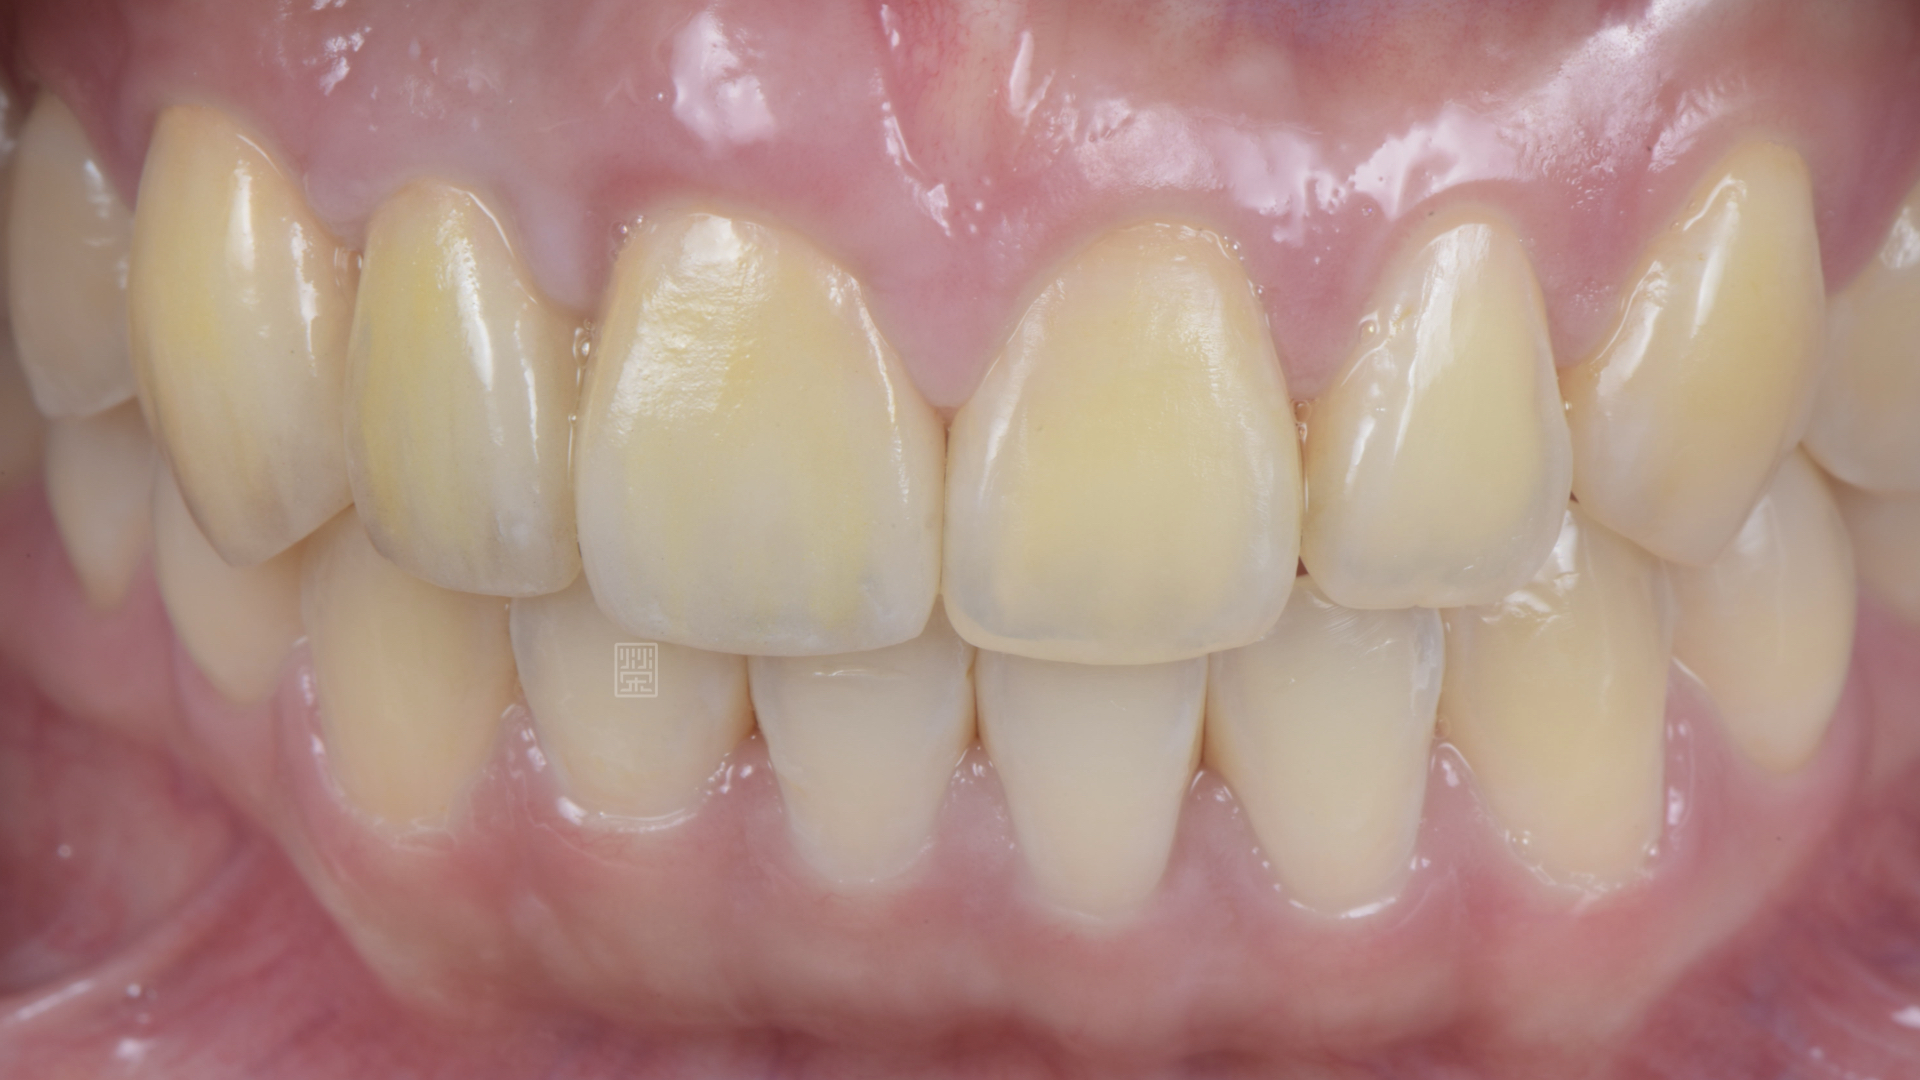

由於門牙本身偏短,藉由微笑分析,決定由牙冠增長術與改變牙齒長度讓門牙達到更好的比例與對稱性,加上側門牙植牙牙齦的調整,並且將右側犬齒用全瓷冠恢復犬齒導引,達到保護性咬合,對未來咬合性穩定性更有幫助。

全瓷冠、植牙全瓷冠完成